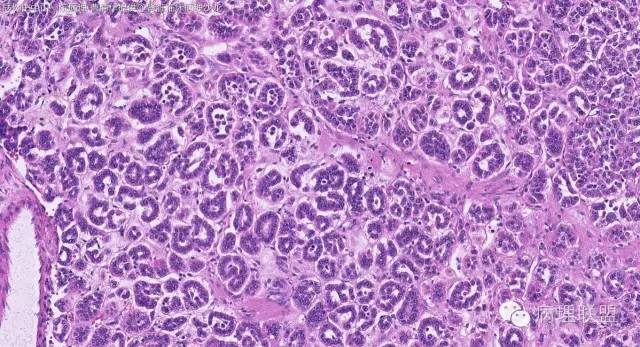

女性,50岁,肾上腺肿物(影像及手术均确认肿物位于肾上腺,界限清楚)。血压升高。(病例由 中山一院病理 曹清华提供,致谢!)

伴假腺样结构的肾上腺皮质腺瘤,合并髓脂肪瘤

从肿瘤的位置及镜下与肾上腺皮质的关系看,应该像是皮质来源肿瘤。假腺样结构的皮质腺瘤没有见过,似乎文献也还没查到。另外inhibina, melanA, syn均阴性(肿瘤旁正常皮质阳)感觉有点迷惑。。。请老师指教,有相关文献么?@武警嘉兴医院 周泉

假腺样是细胞粘附性差了导致。往往可以伴随黏液成分,组化上这几个抗体应该至少会有灶性阳性。

这个我再仔细看下。但,我们这例腺管结构不像是粘附差所致,是真的腺管;间质目前还没有看到有间质粘液变性区域;inhibina, syn, menlana是真的不阳,灶性都没有...